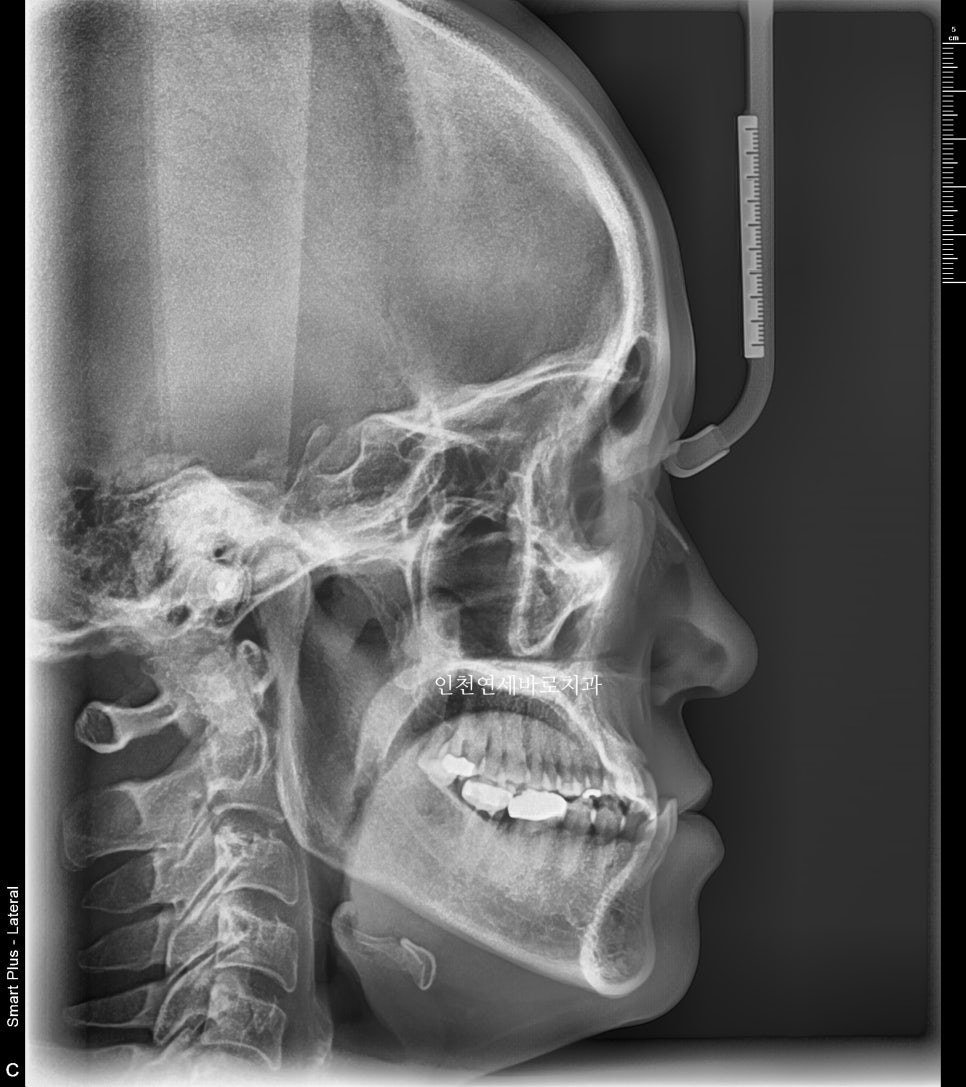

방사선 사진 비교

전후 엑스레이입니다

양악수술은 아니기에 큰 변화는 아니지만 안모의 개선을 확인 가능할겁니다.

양악수술을 하였다면 안모개선 효과가 더 많았겠지만 진단 기준에 따라 수술 없이 주걱턱 교정이 가능함을 보여드리는 포스팅입니다.